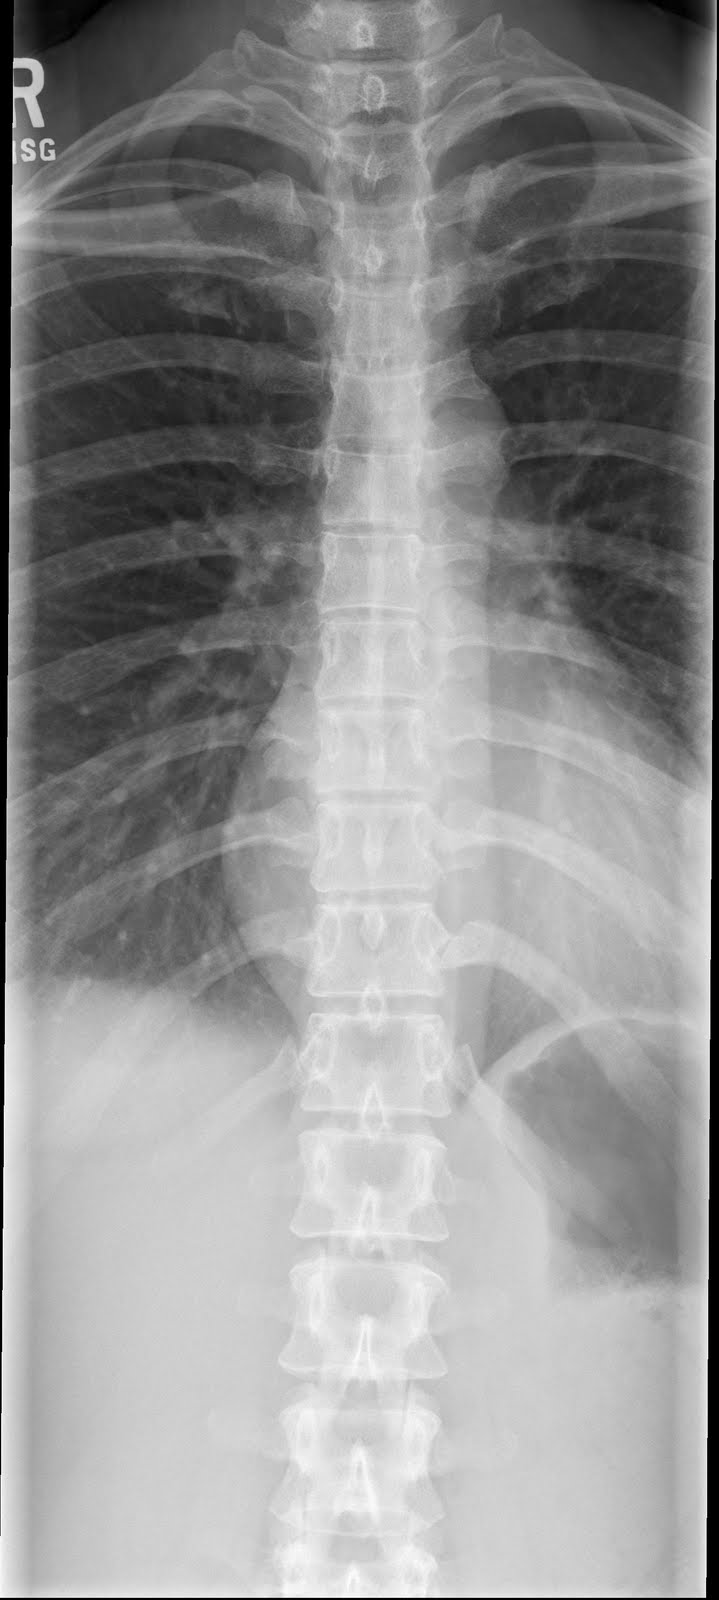

rays at 12.4 years of age. A) Cervical spine Dysmorphic changes of the What Is Focal Bony Abnormality It says nothing about the diagnosis, whether it’s. They can affect any bone and be either benign (harmless) or malignant (cancerous). What is the difference between a benign. Focal sclerotic lesions can affect the cortex and medullary cavity. What is a bone lesion? Growth abnormalities in bone tissue known as bone lesions may be benign or malignant. Bone erosions, or. What Is Focal Bony Abnormality.